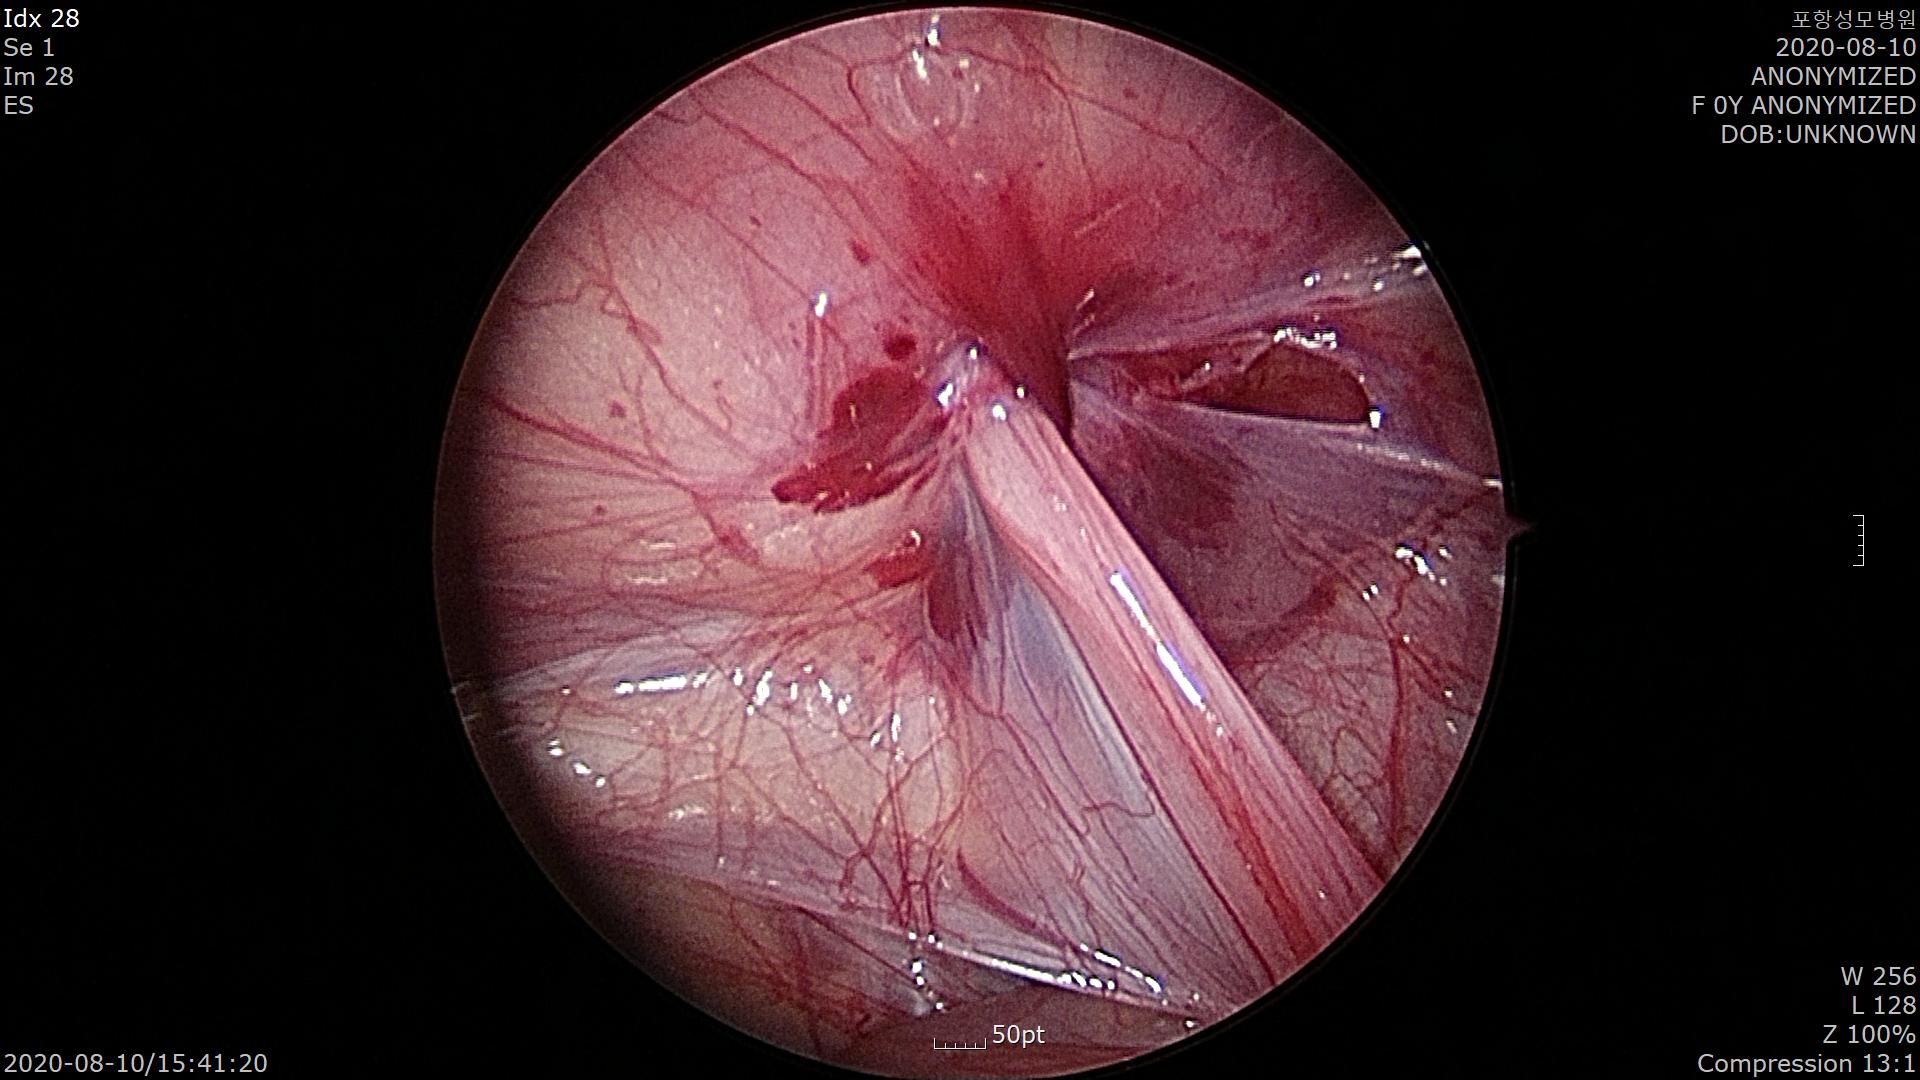

반대편 서혜부를 확인해 보니 왼쪽에도 탈장이 있네요. 이렇게 한쪽 탈장 수술 중 반대편이 발견되는 경우가 약 40%정도 됩니다. 꽤 많습니다.

이럴 때는 복강경 수술이 참 좋습니다. 개복 수술 때는 반대편 탈장을 확인 할 수가 없지요.

잘 봉합했습니다.